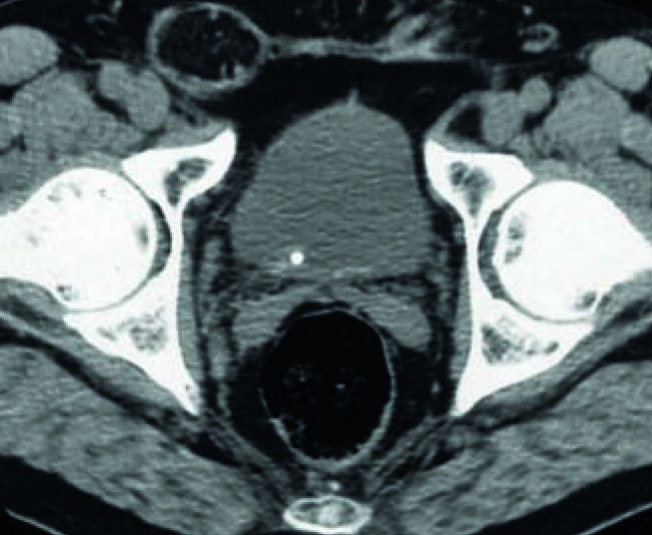

Le scanner sans injection est très performant pour le diagnostic de colique néphrétique : ses sensibilité et spécificité sont élevées, comprises entre 96 et 100 %. Outre le calcul (taille et densité en unités Hounsfield, UH) et sa localisation précise, il met en évidence une dilatation pyélocalicielle et une néphromégalie avec infiltration de la graisse périrénale et péri-urétérale (fig. 2). C’est l’exploration de référence avant un traitement urologique afin de préciser au mieux la morphologie des voies urinaires et les caractéristiques du calcul. Un examen des voies urinaires avec injection est également recommandé avant de traiter un calcul. 2-4